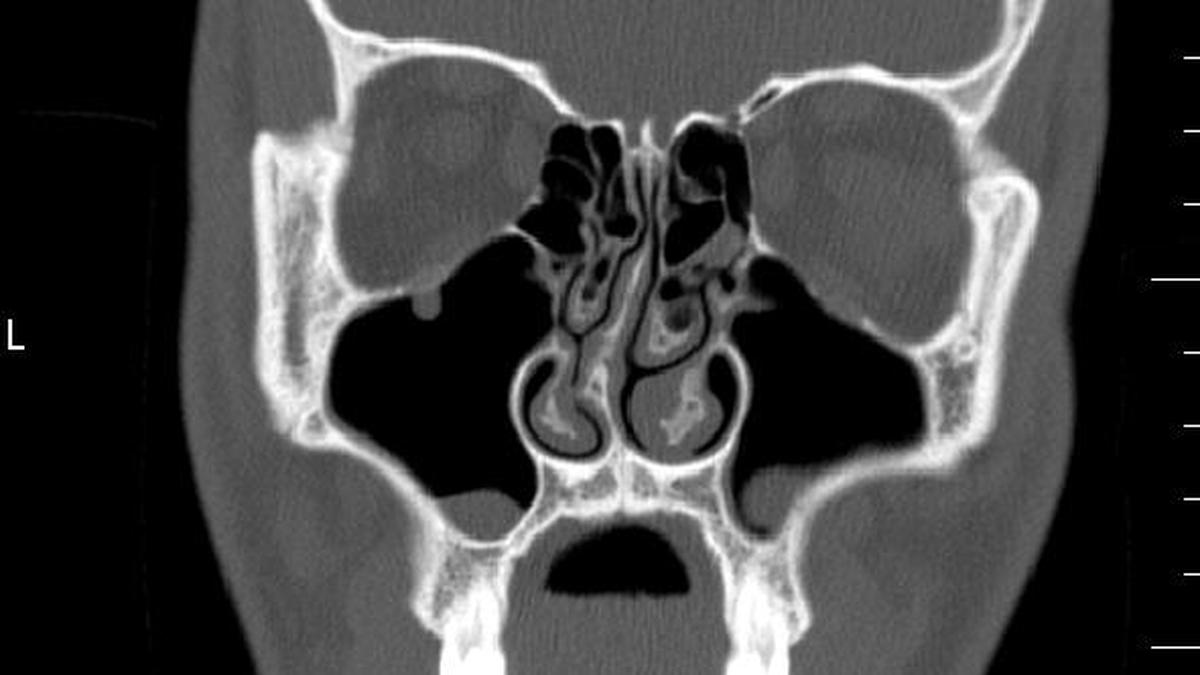

Deviated septum in India: prevalence, causes, symptoms, diagnosis, treatment, and misconceptions explained by ENT specialists concisely.